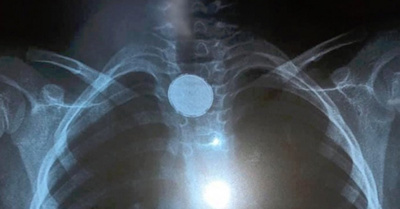

Popular / ¡Cuarto caso en el año! Mitã'i ijahy'opa'ã con moneda de 100'i

¡Jeyma! Dos niños de 9 y 3 añitos y con diferencia de pocas horas, fueron salvados por galenos del Instituto Nacional de Enfermedades Respiratorias y del Ambientes (INERAM) dónde le practicaron un procedimiento para extraerle una moneda de 100 y de 100... [Leer más]